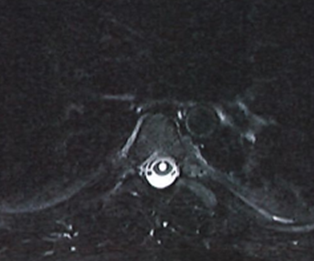

Spine:

Thoracic Spinal Cord Tumor Case Presentation

Author: Xavier P. J. Gaudin D.O., F.A.C.O.S., Read More!